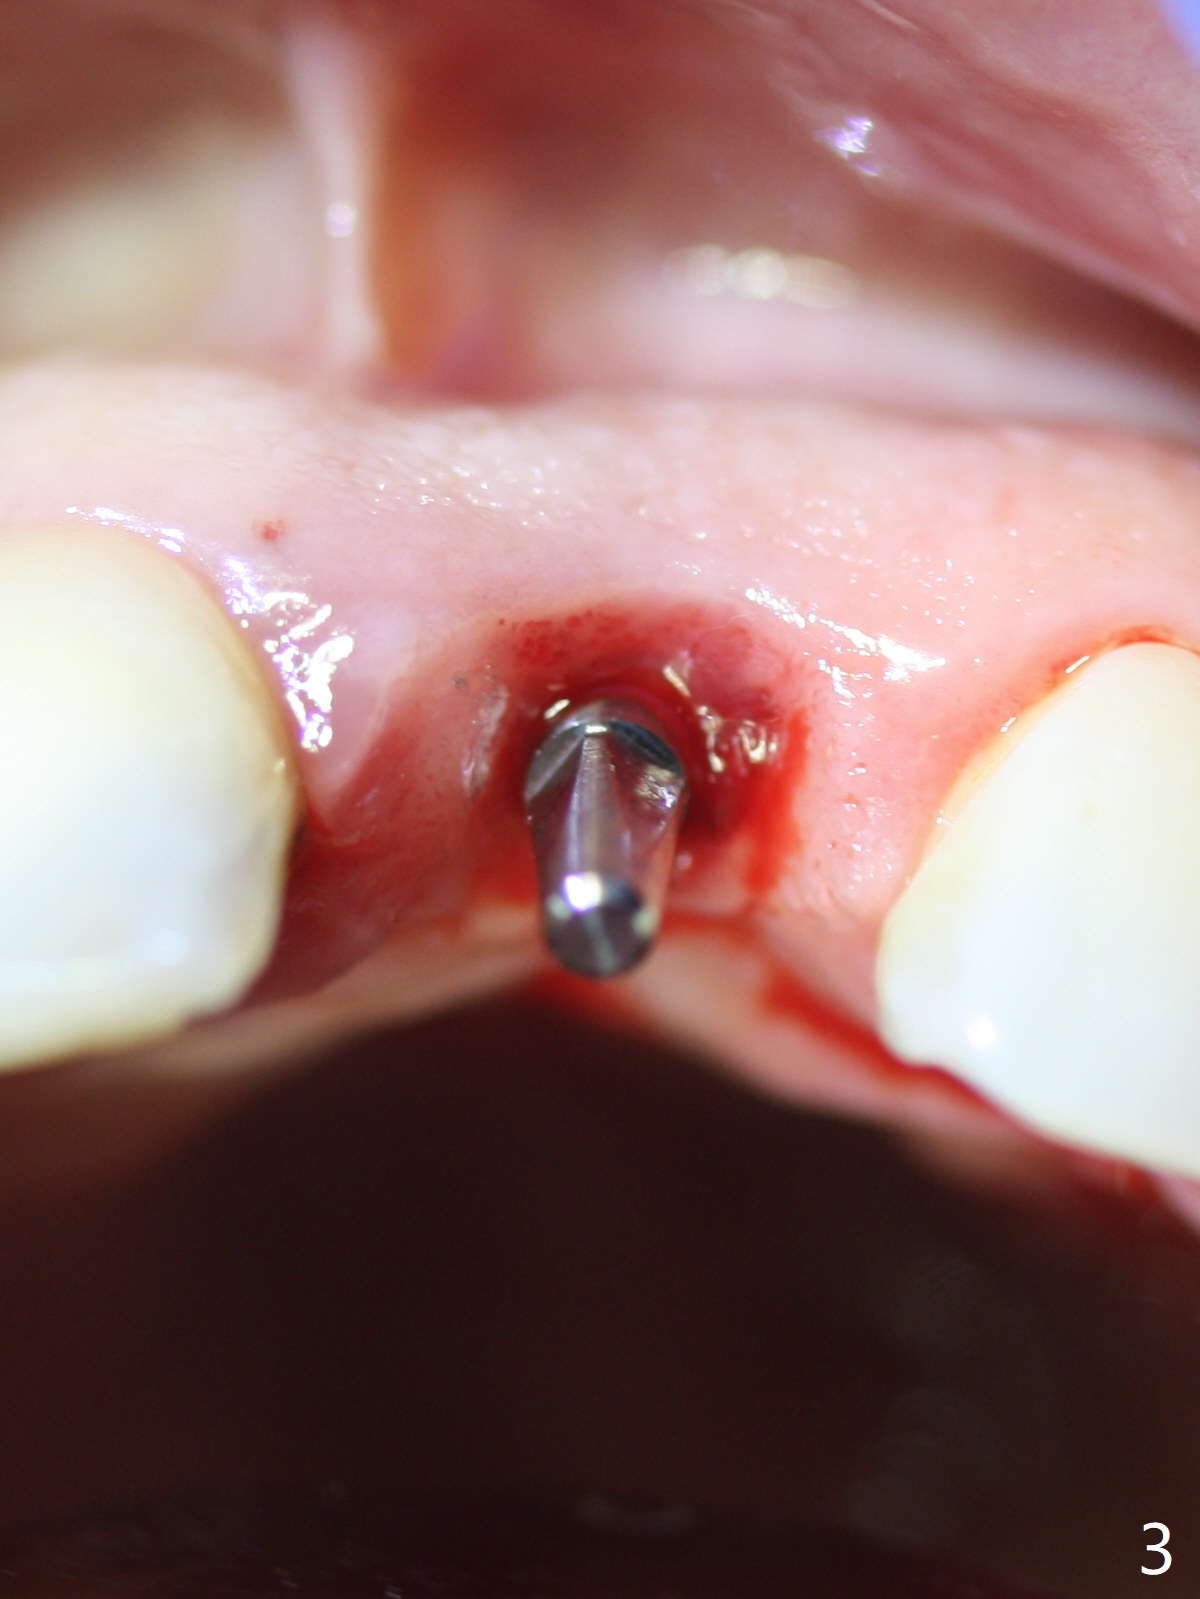

Except the depth, a 2.5x10 mm mini implant is placed with precision (in trajectory) at #9 (Fig.1-5). Confidence using surgical guide for the narrow ridge is enhanced due to placement of two digits against the buccal and palatal plates for tactile sensation. The depth issue is related to overprep with 2.2 mm drills. The torque is <15 Ncm. The immediate provisional is bonded to the neighboring teeth for retention. It appears that smaller drills should be made for guided surgery (such as 1.5 and 2.0 mm). The immediate provisional looks acceptable buccal and occlusal 3 weeks postop (Fig.6,7), although the palatal gingiva is erythematous (Fig.8, which is common after use of drill for access (tissue laceration), OHI offered). Three months postop (Fig.9), the palatal gingiva looks healthy (data not shown), while there is no bone loss around the implant (Fig.10). It remains the same 5 months postop (immediately post cementation, Fig.11) and 3,11 months post cementation (Fig.12,13). The labial gingiva is healthy (Fig.14), while the palatal one is less erythematous and edematous (Fig.15) than earlier (Fig.8).